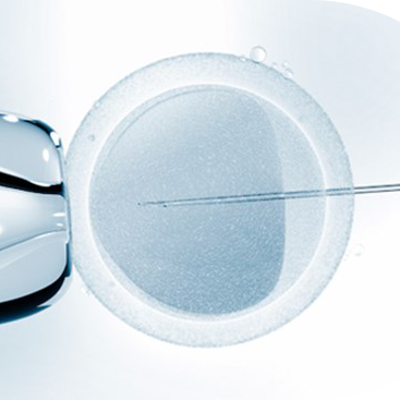

In Vitro Fertilisation (IVF)

IVF using a sperm donor

IVF enables family formation for different types of couples and single individuals.

IVF enables family formation for different types of couples and single individuals.

Doctors can carefully monitor and optimize the fertilization process and embryo development.

Doctors can carefully monitor and optimize the fertilization process and embryo development.

IVF enables family formation for different types of couples and single individuals.

IVF enables family formation for different types of couples and single individuals.

Doctors can carefully monitor and optimize the fertilization process and embryo development.

Doctors can carefully monitor and optimize the fertilization process and embryo development.